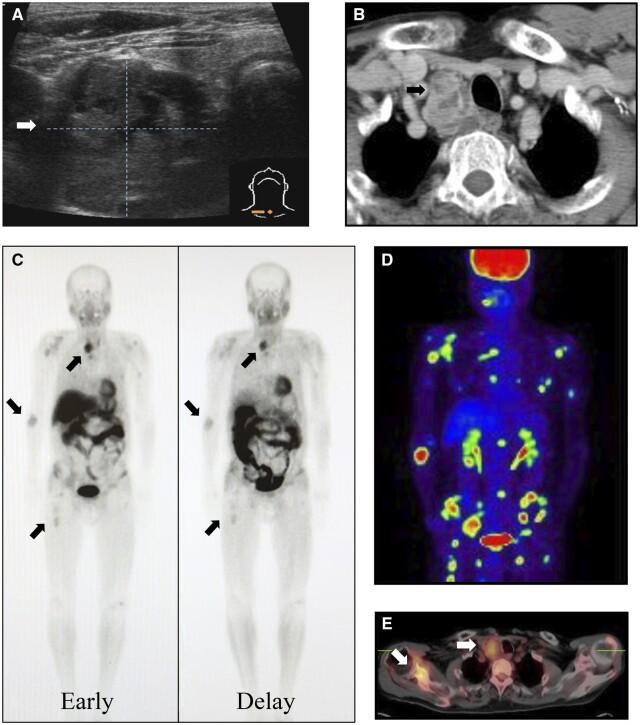

We present two rare cases of parathyroid carcinomas associated with multiple brown tumours. Plain radiographs, computed tomography, and neck ultrasonography revealed the presence of bone and parathyroid tumours. Despite the use of 99m Tc-methoxy isobutyl isonitrile (99mTc-MIBI) or F-fluorodeoxyglucose-positron emission tomography (18F-FDG PET)/CT, it was difficult to differentiate bone metastases from brown tumours. Parathyroid carcinoma was confirmed by histopathological examination following parathyroidectomy, resulting in spontaneous bone lesion improvement. In patients with parathyroid carcinoma presenting with bone lesions suggestive of metastasis, understanding the potential for brown tumour accumulation through 99mTc-MIBI or 18F-FDG PET/CT is pivotal. With this understanding, it is possible to diagnose brown tumours with parathyroidectomy and follow up for improvement of bone lesion and avoid invasive biopsy or surgery.

我们报告两例罕见的与多发性棕色瘤相关的甲状旁腺癌病例。X线平片、计算机断层扫描和颈部超声检查发现存在骨骼和甲状旁腺肿瘤。尽管使用了99m锝-甲氧基异丁基异腈(99mTc-MIBI)或氟-氟脱氧葡萄糖-正电子发射断层扫描(18F-FDG PET)/CT,但很难区分骨转移瘤和棕色瘤。甲状旁腺癌经甲状旁腺切除术后的组织病理学检查得以确诊,随后骨骼病变自发改善。对于表现出提示转移的骨病变的甲状旁腺癌患者,通过99mTc-MIBI或18F-FDG PET/CT了解棕色瘤积聚的可能性至关重要。有了这种认识,就有可能通过甲状旁腺切除术诊断棕色瘤,并对骨病变的改善情况进行随访,避免进行侵入性活检或手术。